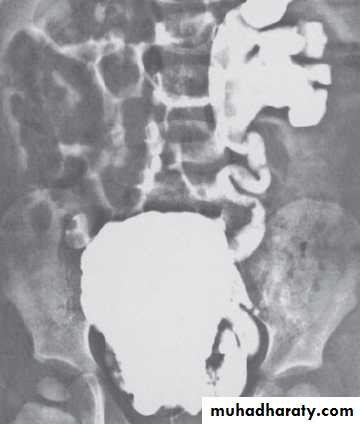

U.S. , IVU, MCUG( it shows the valve folds, the trabeculated bladder with diverticulae & even vesicoureteral reflux).Cystourethroscopy confirm the Dx.